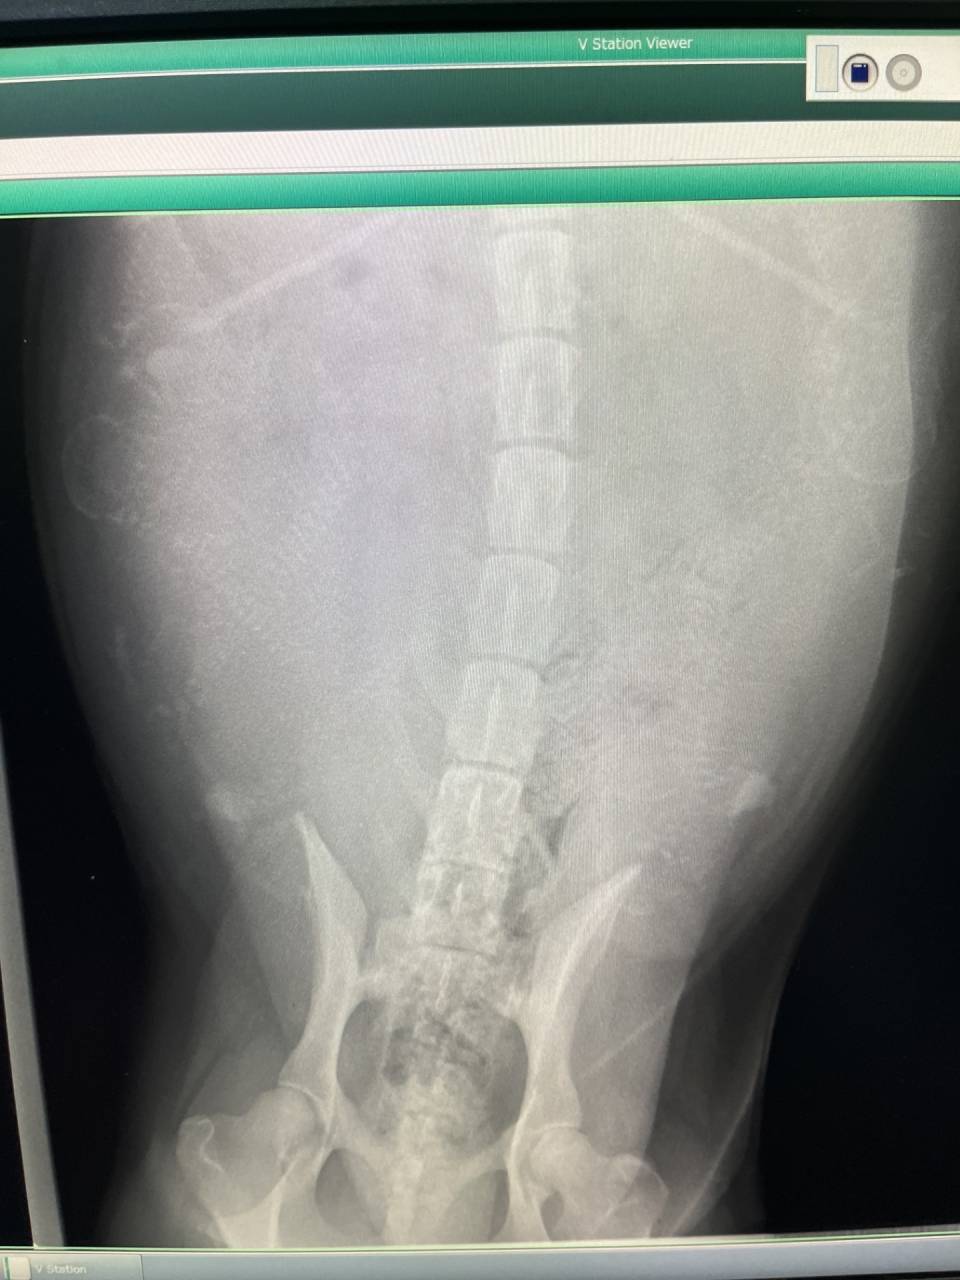

エルちゃん、バッチリ!!8~9匹+アルファ・・・

股関節も凄く良いし、あとは、エルちゃんの体力次第ですね。頑張れ!!!